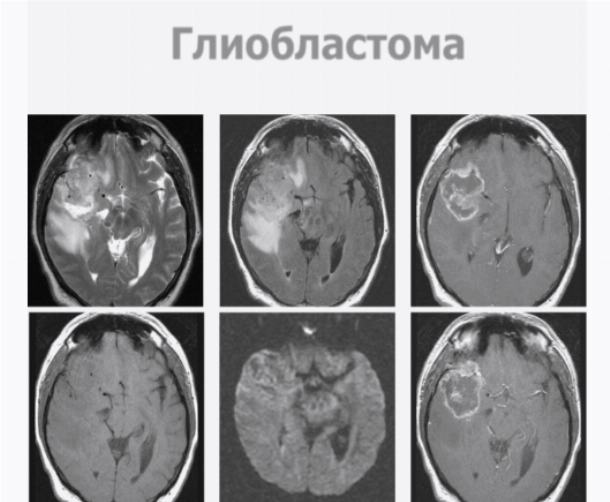

Для глиобластом характерно беспорядочное скопление клеток опухоли с увеличенным количеством ядер, которые перемежаются с очагами некроза и измененных сосудов.

Данный вид злокачественного образования, появляющегося в головном мозге, очень опасен по причине быстрого роста и отсутствия четких разграничений между пораженными и здоровыми тканями.

- МРТ мозга, КТ с контрастным веществом. Эти способы помогают установить локализацию опухоли, обширность распространения.